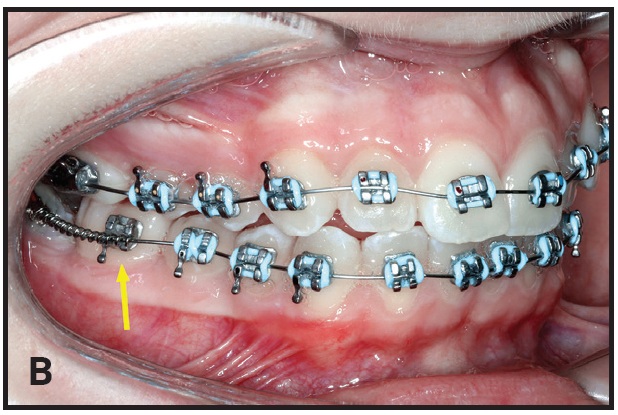

A mandibular second-premolar twin bracket is bonded to the mesiobuccal cusp of the first molar. The bracket’s curved base adapts nicely to the molar surface (B). Using a twin bracket instead of a standard first-molar tube makes it easier to thread the archwire through the second-molar tube and compress the open-coil spring (C). Moreover, the spring can be placed over the initial nickel titanium wire at the bonding appointment.